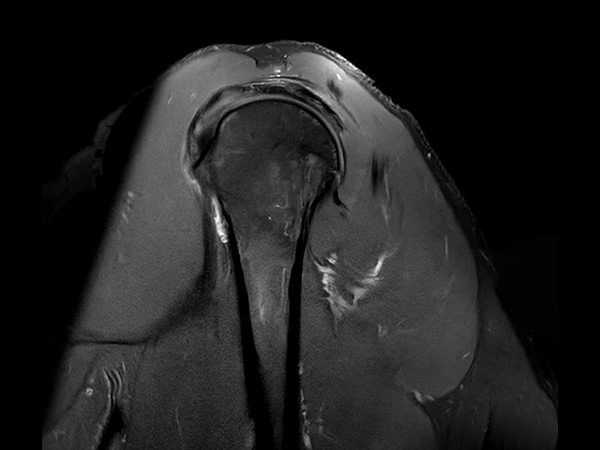

High quality Shoulder imaging with SmartSpeed Precise